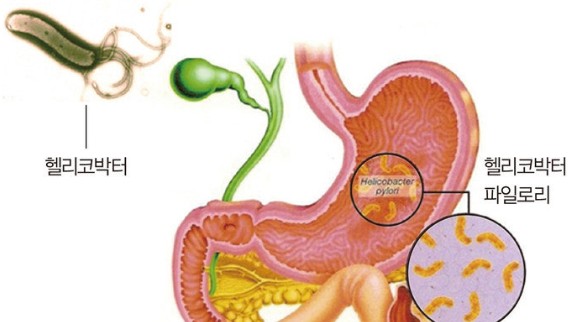

"식사만 하면 속이 쓰리고, 더부룩한 느낌이 사라지지 않나요?"단순한 소화불량이라 넘기기 쉬운 증상들이 사실은 헬리코박터 파일로리균(H. pylori) 감염 때문일 수 있습니다.특히 위염이나 위궤양을 자주 앓는다면 이 균에 감염되었는지 반드시 확인해보아야 합니다.이 글에서는 헬리코박터균의 정확한 정체부터 감염 증상, 검사 방법, 치료법, 그리고 재감염을 막는 생활 습관까지 꼭 알아야 할 정보를 자세히 소개합니다.∴ 헬리코박터균이란? – 위 속에 사는 유일한 세균헬리코박터 파일로리균은 위 점막에 서식하는 나선형 세균으로, 위산 속에서도 살아남는 독특한 생존력을 가졌습니다.세계보건기구(WHO)는 이 균을 1급 발암물질로 지정했을 만큼 위암과의 연관성이 높습니다.☞관련질환:만성 위염위궤양, 십이지장궤양위암기능..